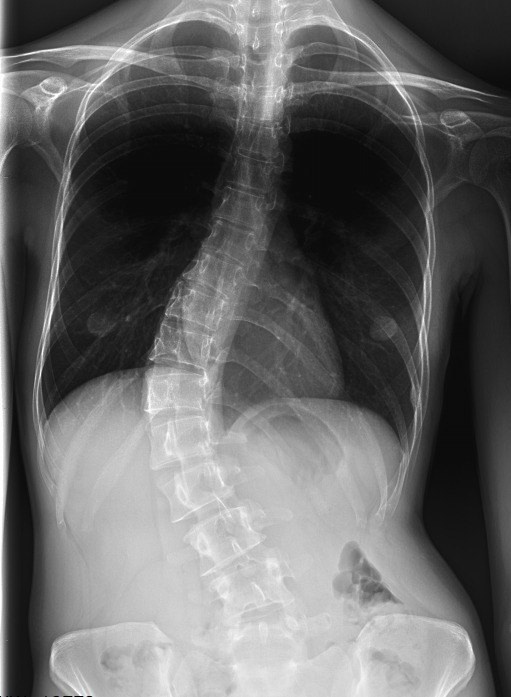

Возможности российской системы для коррекции сколиотических деформаций

Комбинация униаксиальных и полиаксиальных винтов в сочетании с многофункциональным деротационным набором позволяет проводить многоплоскостные манипуляции на имплантах существенно расширяя арсенал современного вертебролога.

• Одномоментная деротация на стержне и на униаксиальных винтах даёт максимальный эффект контроля дуги искривления.

• При этом появляется возможность сократить количество фиксированных позвонков и проводить более селективную фиксацию, что крайне важно для сохранения подвижных сегментов после операции.